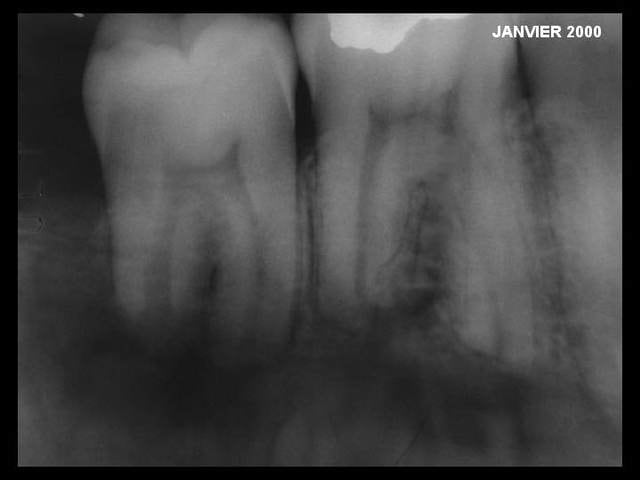

y a deux autres radios que voilà ...

Rx2 uhbjgr - Eugenol